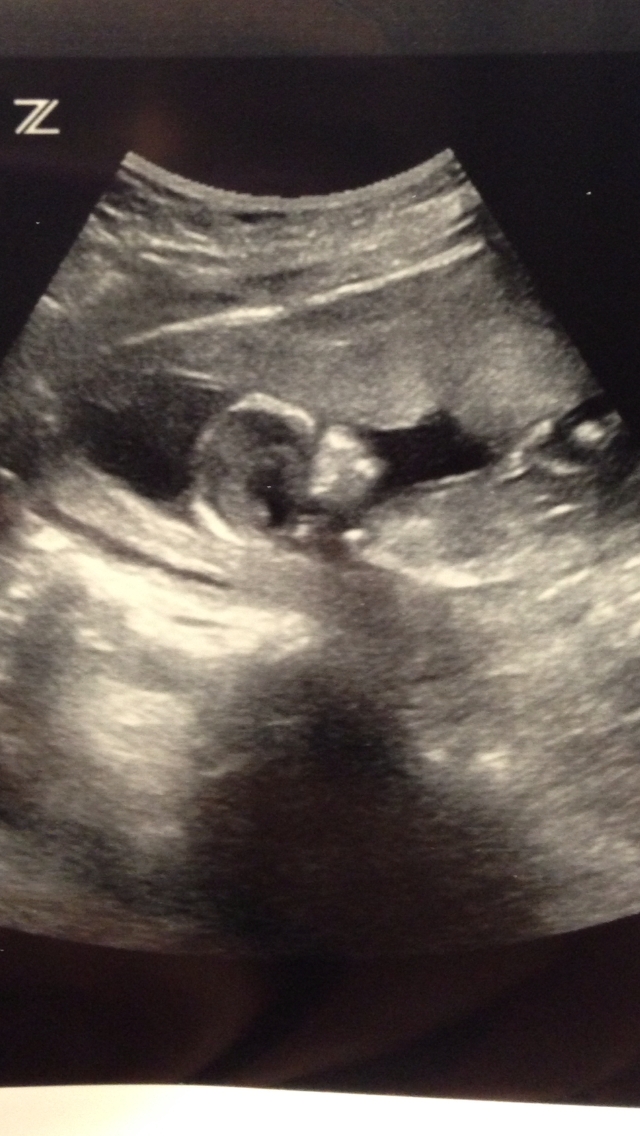

Here is a photo of my little one at 12 weeks:

Attachment 8863